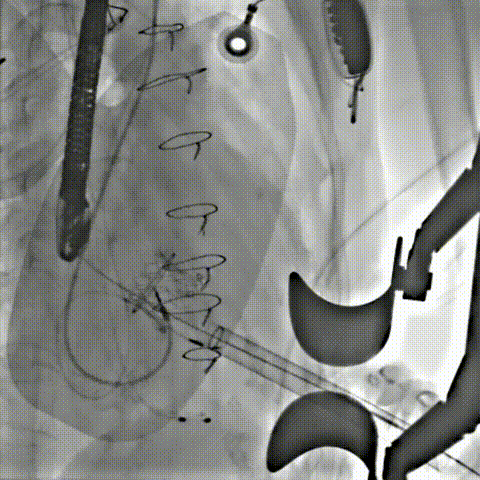

术中影像

球扩释放

释放后

6atm球扩释放,植入Renatus 23#,瓣架形态良好,位置理想。